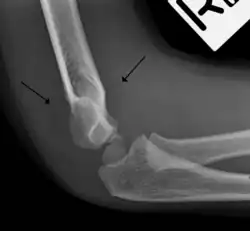

Pathophysiology

The posterior fat pad is normally pressed in the olecranon fossa by the triceps tendon, and hence invisible on lateral radiograph of the elbow.[3] When there is a fracture of the distal humerus, or other pathology involving the elbow joint, inflammation develops around the synovial membrane forcing the fat pad out of its normal physiologic resting place. This is visible as the "posterior fat pad sign" and is often the only visible marker of a fracture, particularly in the pediatrics population.